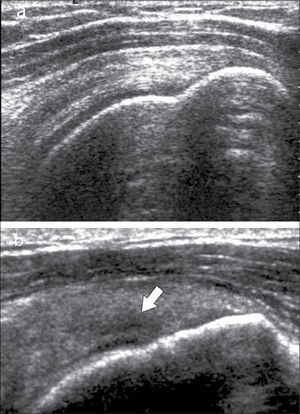

El tendón de Aquiles por sus características anatómicas y función particulares, a veces genera un examen ecográfico propio. Puede manifestar patología de distintas maneras, además de la tendinopatía similar a los otros tendones, incluso cálcica, en el tendón de Aquiles se puede encontrar engrosamiento del peritendón (no tiene vaina sinovial), aumento de vascularización, bursitis periaquilianas, alteraciones en la grasa de Kager, roturas parciales intrasustancia o completas en tercio medio o en la unión miotendínea con el tríceps sural (figura 11) (28).